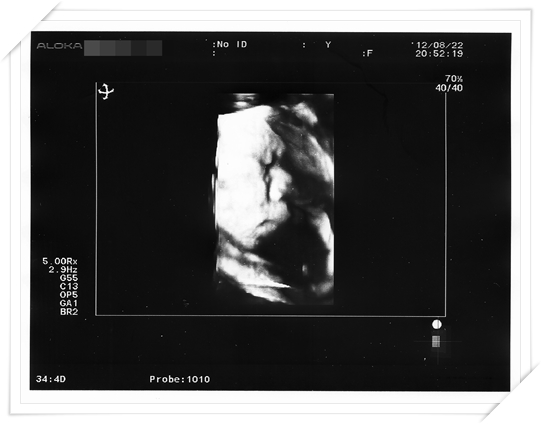

最後 醫生還順便奉送了幾張4D 的照片

因為他說 之前照高層次的時候 臭小鴨都不配合把臉轉過來

可是這天 可能他太胖啦 也轉不太過來了

醫生照了好久 勉強照了這兩張

恩 看看他的肉肉臉 果然 破兩千公克不是假的

肥嘟嘟的臉頰 跟之前差也太多了吧!!